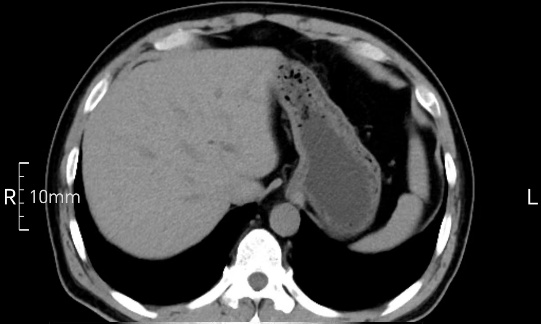

看看下面三幅便知遵醫(yī)囑的重要性。

完美禁食且喝飽飽,胃壁完美展現(xiàn)。